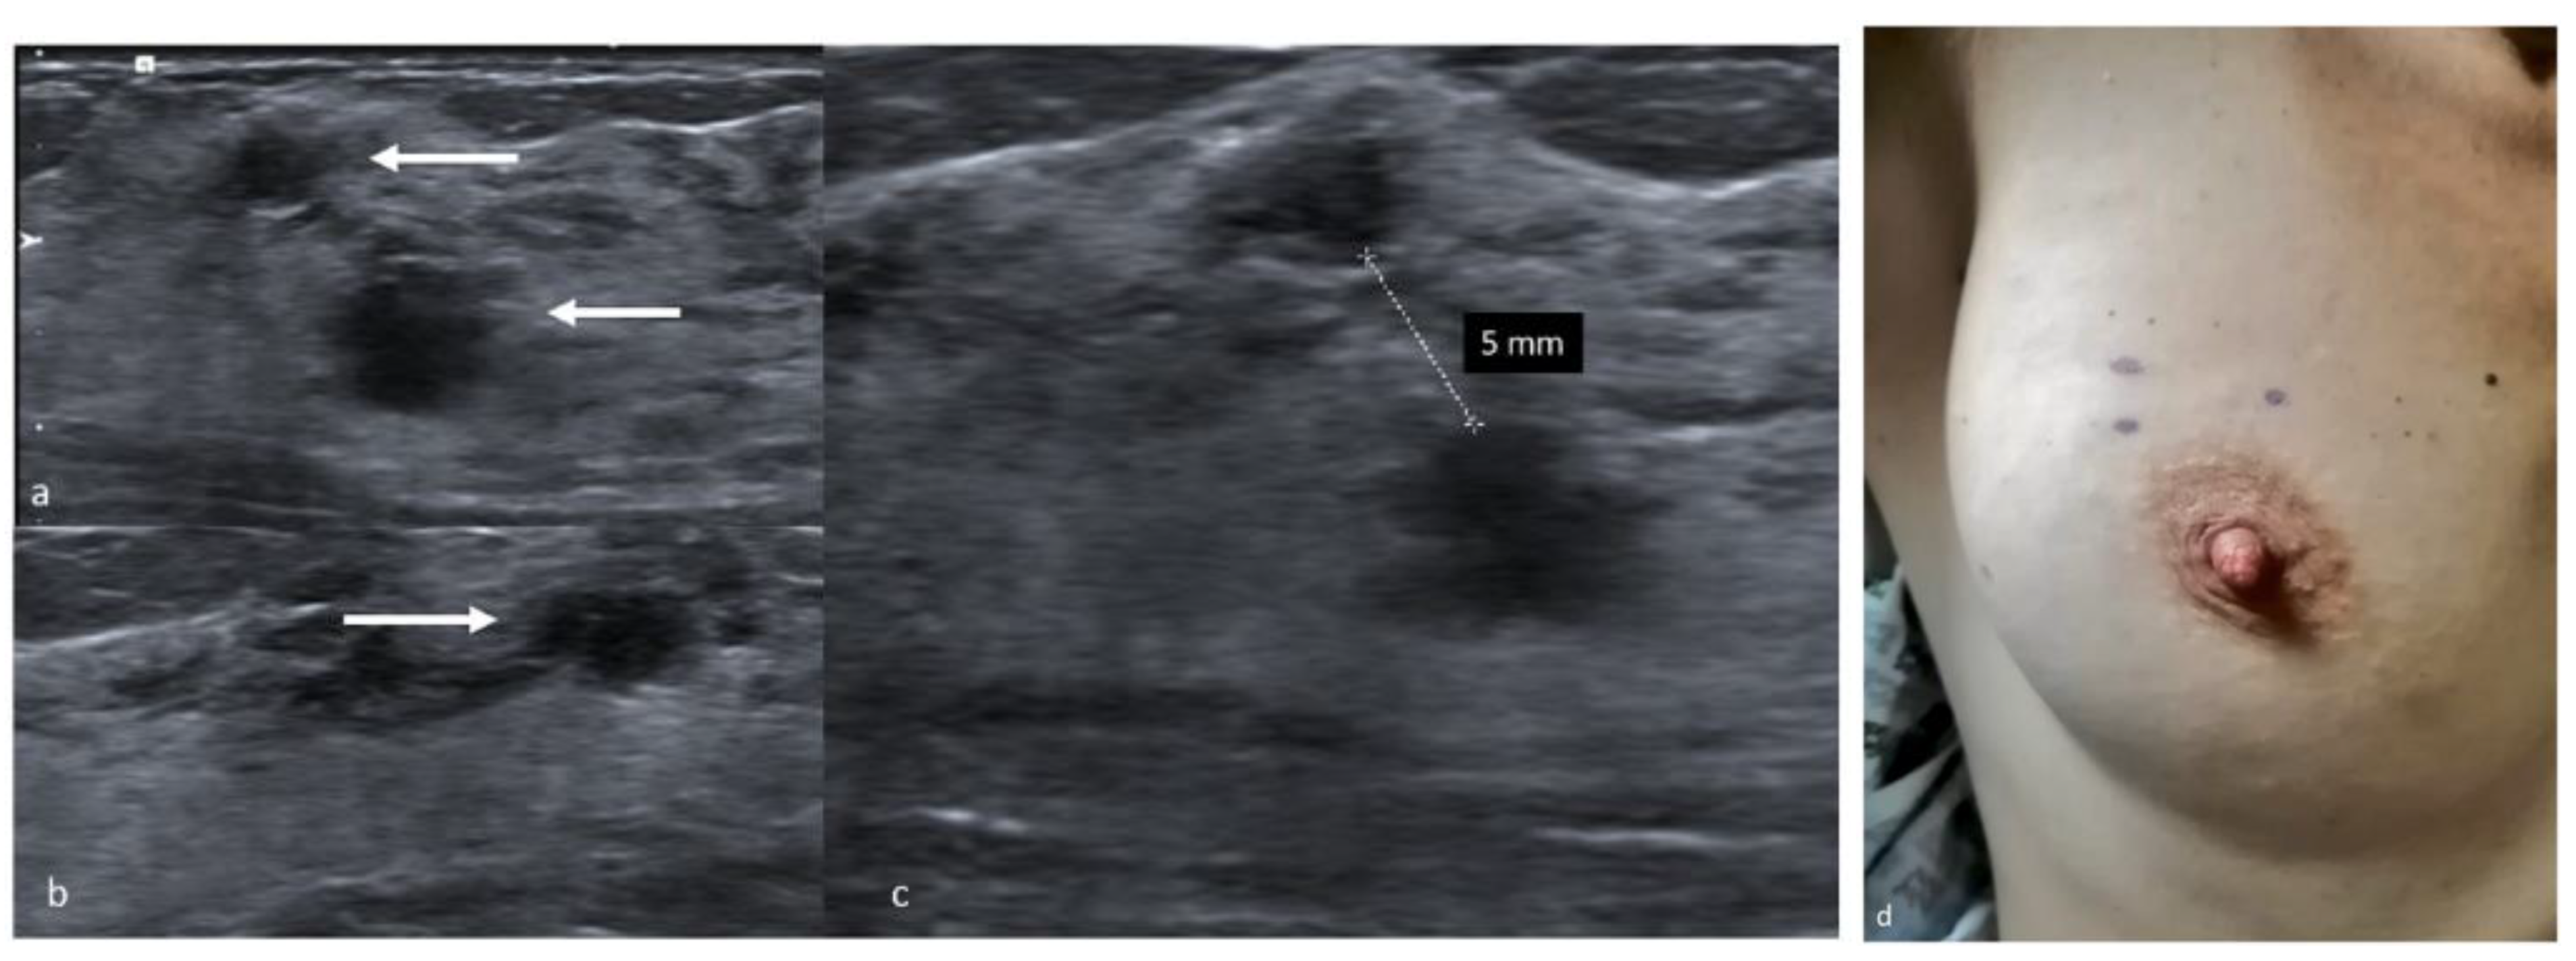

3. Carbon Marking